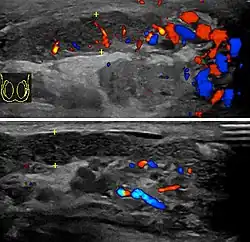

At ultrasound, the findings of acute epididymitis include an enlarged hypoechoic or hyperechoic (presumably secondary to hemorrhage) epididymis [Fig. 20a]. Other signs of inflammation such as increased vascularity, reactive hydrocele, pyocele and scrotal wall thickening may also be present. Testicular involvement is confirmed by the presence of testicular enlargement and an inhomogeneous echotexture. Hypervascularity on color Doppler images [Fig. 20b] is a well-established diagnostic criterion and may be the only imaging finding of epididymo-orchitis in some men.

Doppler ultrasound of epididymitis, seen as a substantial increase in blood flow in the left epididymis (top image), while it is normal in the right (bottom image). The thickness of the epididymis (between yellow crosses) is only slightly increased (7 mm).

Doppler ultrasound of the scrotum of the same case, in the axial plane, showing orchitis (as part of epididymo-orchitis) as hypoechogenic and slightly heterogenic left testicular tissue (right in image), with an increased blood flow. There is also swelling of peritesticular tissue.